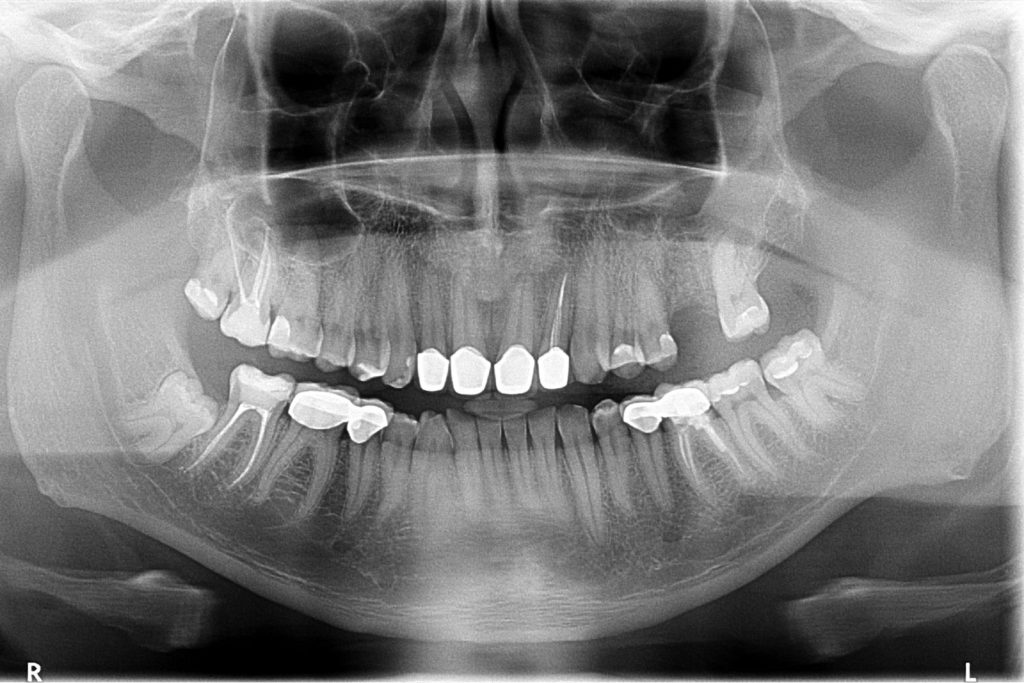

Przed podjęciem leczenia należy określić stopień zaniku kości szczęk oraz żuchwy. W tym celu przeprowadza się badanie kliniczne oraz odpowiednią diagnostykę obrazową pacjenta. Uwzględnia ona zdjęcie panoramiczne OPG jako podstawę dwuwymiarowego obrazowania podłoża kostnego oraz możliwe jest badanie tomograficzne CT lub bardziej precyzyjna tomografia stożkowa CBCT. Opcjonalnie wykorzystywana diagnostycznie tomografia pozwala na bardziej wnikliwą ocenę stopnia zaniku kości w trójwymiarowym, przestrzennym obrazie.